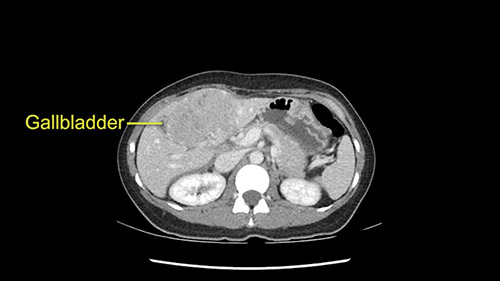

As I review the CT scan, we have both arterial and venous phases, the tumor is obvious. But I’ll start by saying that the liver itself does not appear to be cirrhotic to my eye. It’s got a normal contour and allied to that, that I do not see evidence of portal hypertension. The spleen is normal, there’s no collateral vessels. The tumor itself, I measured maximally at about 11 centimetres in diameter and I’m told the alpha fetoprotein is very high (over 10000), which is entirely consistent with this being a solitary hepatocellular carcinoma that is very exophytic. It seems to emanate off the inferior margin of Segment 3 (because that’s the falciform). I’ll start by saying that this is not transplantable. The tumor exceeds our guidelines for transplantation, but it's likely resectable based on normal liver and no portal hypertension.

We note that the tumor is pushing on the gallbladder but I think that’s probably external for the most part. I think that’s extrahepatic. I believe that Segment 4b is probably free of tumor. I’d have to say that it's tempting, particularly looking at the coronals, to consider a very limited resection. Where you’d just chip it off the bottom of Segment 3 and do a limited Segment 3 resection. I’d be concerned about the oncologic margins. I believe that the best oncologic operation will be to take the left portal vein to get this. Certainly, she’s got plenty of liver and she’d be able to sacrifice Segments 2-3 of the left lobe of the liver. It’s not necessary to take too much of thus of Segment 4a. But once one takes the portal vein, that will be compromised. So I would do a left hemihepatectomy on this woman.

When you see the axial sections of the scan, you find it's a largely exophytic mass and its well-encapsulated. So this is typically true of a well-differentiated hepatocellular carcinoma. If you look at this, this is the gallbladder which is being displaced to the right and the mass is in the Sg4 of the liver, exophytic, projecting down. As it is coming down, it is also displacing the duodenum and the head of the pancreas which is being pushed towards the left and it's going right up to the cava, the start of the anterior surface of the cava. Obviously getting a lot of collaterals and vascularity from all the vessels around but one has to be very careful in evaluation of the main portal pedicle in this particular case and of course arterial inflow to the Sg4 and of course the left lobe of the liver.